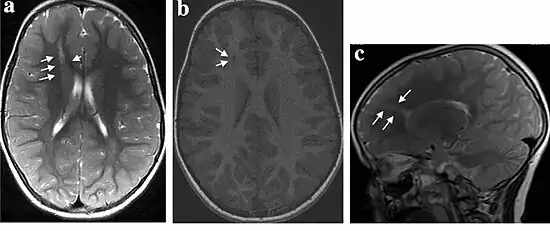

Subcortical heterotopia a–c) Non-contrast enhancement magnetic resonance imaging

Subcortical heterotopia form as distinct nodes in the white matter, "focal" indicating specific area. In general, patients present fixed neurologic deficits and develop partial epilepsy between the ages of 6 and 10. The more extensive the subcortical heterotopia, the greater the deficit; bilateral heterotopia are almost invariably associated with severe developmental delay or intellectual disability. The cortex itself often has an absence of gray matter and may be unusually thin or lack deep sulci. Subependymal heterotopia are frequently accompanied by other structural abnormalities, including an overall decrease in cortical mass. Patients with focal subcortical heterotopia have a variable motor and intellectual disturbance depending on the size and site of the heterotopion.